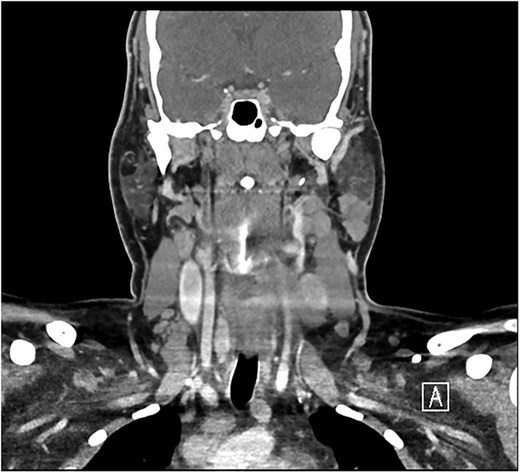

A 28-year-old man with a BMI of 44.3 kg/m2 and, a history of hypertriglyceridemia on gemfibrozil 600 mg complained of neck swelling for 2 years. It began as a nodular swelling at the right supraclavicular region and later spread to the right axillary and left supraclavicular areas. For one month, the patient had an unintentional weight loss of 4 kg and a few episodes of night sweats but no fatigue, fever, or compressive symptoms. He never received any radiation treatment. The family history was positive for an aunt with a malignant thyroid disease, for which she had a total thyroidectomy done. He was also on calcium carbonate 1200 mg orally thrice daily and levothyroxine 200 mcg orally once daily. On general examination, the patient did not look dehydrated, the patient was afebrile and did not appear to be in acute respiratory distress. There was a firm, nontender, nonmobile mass in the right anterior neck which represents lower cervical lymphadenopathy. No thyroid nodules, thrills, or shift of the trachea to the right were found. Abdominal examination was normal, that is, no enlargement or tender masses were felt on abdominal palpation. It started in January 2018 with right sided lymph node enlargement and a detailed assessment was done at a hospital in the United Kingdom (UK) in March 2020. FNA of the neck nodes showed features of HL and the thyroid US showed a hypoechoic nodule with punctate calcifications measuring 3.9 × 1.9 cm and TI-RADS 5. Other findings were bilateral clinically suspicious cervical lymphadenopathy; the largest nodes being 3.6 × 2 cm on the right side and 2.8 × 1.3 cm on the left side. The laboratory findings included T3 of 5.19 pmol/L, T4 of 25 pmol/L, and thyroid stimulating hormone (TSH) of 0.817μIU/ml. According to these observations, the patient underwent further investigations and imaging, CT of the chest revealed necrotic mediastinal, bilateral axillary, and subpectoral lymph nodes suggesting intrathoracic metastases most probably from PTC or lymphoma (Fig. 1). A nuclear medicine scan confirmed FDG-avid disease in the thyroid and nodal areas above the diaphragm. A subsequent FNA of the thyroid nodule revealed papillary thyroid carcinoma (Fig. 2). The patient had a total thyroidectomy, central compartment lymph node dissection, and excision in March 2020. Surgical pathology showed PTC in the right thyroid lobe measuring 2.5 cm in diameter and ipsilateral cervical lymph node involvement. The postoperative treatment included radioactive iodine ablation of 120 mCi in December 2020, and thyroglobulin level was negative. However, the patient got other symptoms by November 2023 after the above-mentioned interventions were conducted. Postoperative US of the neck, done after thyroidectomy, did not demonstrate any thyroid tissue but multiple enlarged cervical lymph nodes, including one that was 2.3 × 1.2 cm in size, with some of the nodes matted and non-encapsulated with loss of fatty hilum. CT imaging revealed an interval increase in the size of right cervical and supraclavicular LN (Fig. 3) and nuclear imaging showed relapsed HL with FDG-avid lymph nodes, above and below the diaphragm. The histopathological examination of the right cervical lymph node excisional biopsy was done and immunohistochemistry staining of markers compatible with CHL was observed (Figs 4 and 5). The tumor cells were positive for CD 30, CD 15 (partially), MUM 1, and PAX 5 (faintly), and the reactive lymphocytes for CD 3 only. The diagnosis of relapse of classical Hodgkin lymphoma (CHL) called for additional oncologic assessment and intervention.

Post-total thyroidectomy and bilateral neck dissection with no signs of recurrence or residual at the thyroid bed. There is a right level IV 11 mm lymph node near the clip of neck dissection.